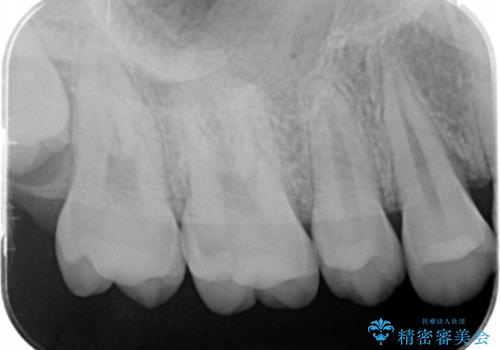

歯と歯の間の虫歯 e-maxインレーで修復

- 歯と歯の間に虫歯が見られたために、拡大鏡下でう蝕を取り除き、e-maxインレーで治療しました。

- e-maxインレー 7.7万円 費用は治療当時の料金となります